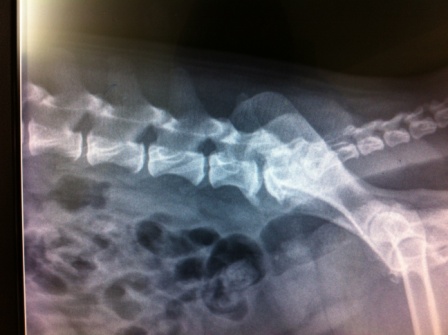

Charlie est un Cairn Terrier mâle de 7 ans, qui depuis quelques semaines a souvent des difficultés à uriner : strangurie et dysurie, tels sont les uniques symptômes lors de la première consult...

Oliver est un chat Exotic Shorthair de 12 ans, adopté assez jeune par sa propriétaire, après un début de vie « difficile » semble-t-il, mais dont on ne sait pas grand chose. Il sort un peu...